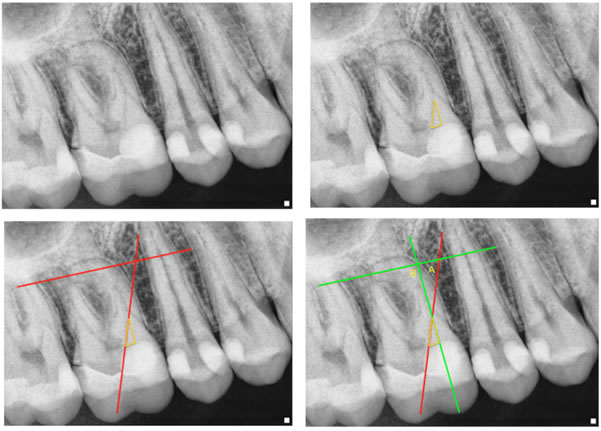

Also see figure 3 showing the dentin triangles of a recent case from our office. The top left is the pre-operative x-ray, the top right shows the triangle in yellow. The bottom left shows the angle of access without removal of the triangle. The bottom right shows the difference in the angle of access when the triangle is removed.

Figure 3

This triangle of dentin needs to be removed in order to gain a smoother transition for the eventual shaping of the canals.